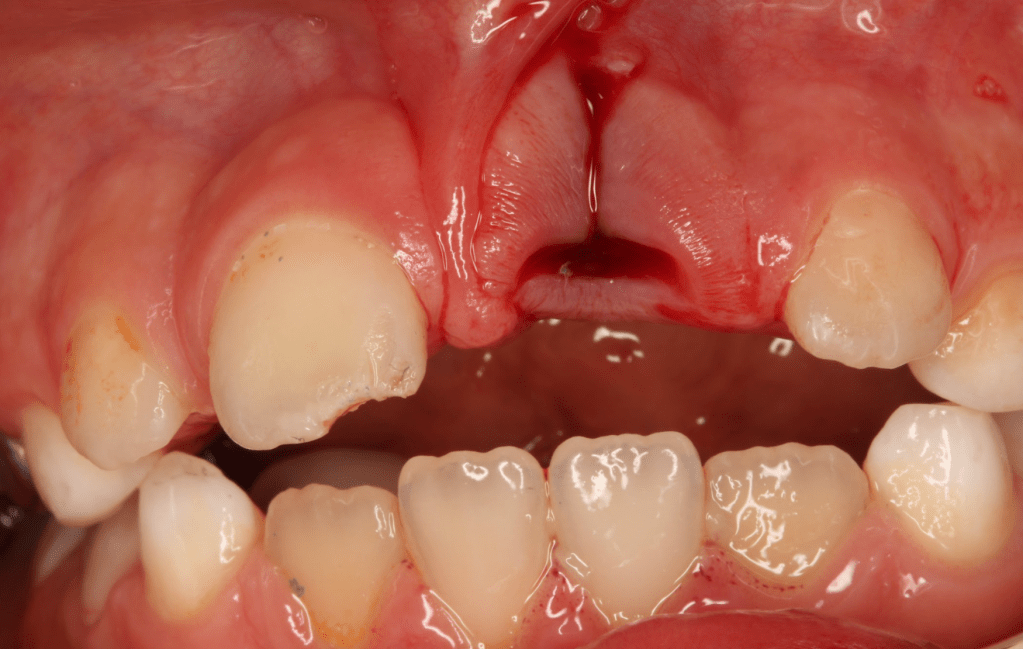

Gingivectomía + pulpotomía biodentine + reconstrucción

Pulpotomía biodentine + reco preendio